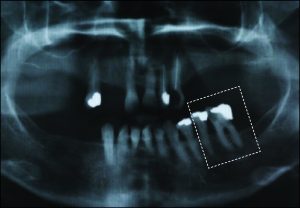

The use of direct retainers on isolated abutment teeth in distal extension PRD cases usually accelerates the destruction of the periodontium, leading to tooth loss. For this reason, it is recommended to place rests on isolated teeth and not to use direct retainers. Another option is restoration of the modification space with a fixed partial denture and splinting of the teeth (Figures 10-15).